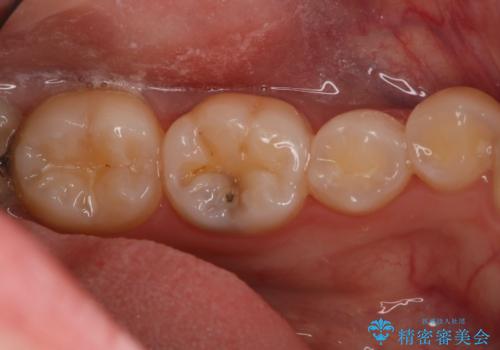

- 10年以上ぶりに歯科に来院された患者です。

口腔内・レントゲン写真からう蝕が見られたので治療を勧めたところ、自費治療を希望されたのでセラミックインレーにて治療を行いました。

左下6番のカリエス除去を行ったところ、深くまで削る必要があったため、CR裏層をした上でセラミックインレー形成をしました。